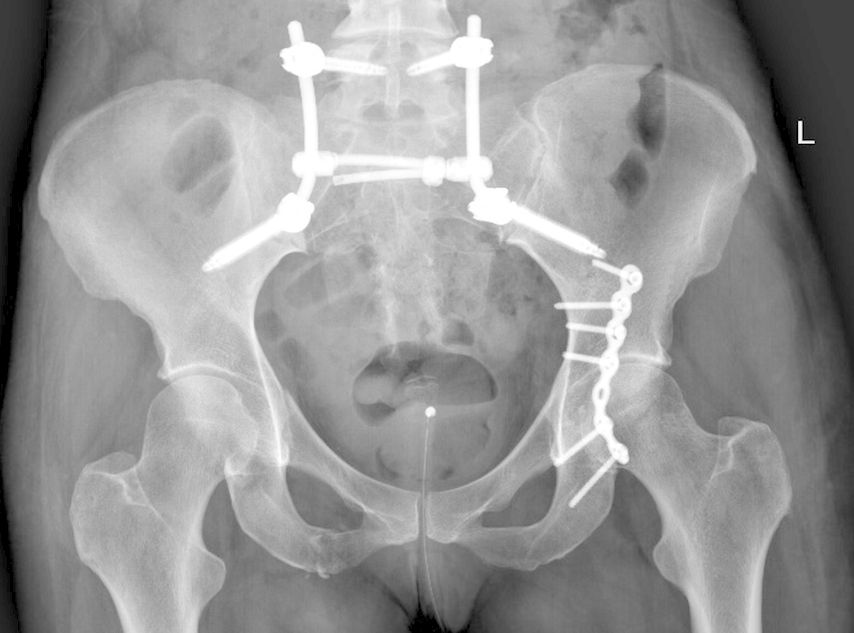

Die lumbopelvine Stabilisierung bietet als etabliertes Verfahren eine hohe biomechanische Stabilität. In diesem Artikel werden anhand der aktuellen Literatur und Empfehlungen die Indikationen, Vor- und Nachteile der lumbopelvinen Stabilisierung sowie die Abwägung mit alternativen Techniken bei Sakrumfrakturen behandelt.

Um die Indikationen der lumbopelvinen Stabilisierung (LPS) zu identifizieren, muss man sich mit den Arten der Sakrumfraktur auseinandersetzen. Die gängigste Klassifikation nach Denis unterscheidet nach der Lokalisation von lateral nach zentral die Denis-I-Fraktur im Bereich der Massa lateralis, Denis II mit Beteiligung der Foramina und Denis III mit zentralen Frakturausläufern. Diese Klassifikation ist hilfreich für die schnelle und einfache Beschreibung von Sakrumfrakturen und ist in erster Linie nützlich für die Abschätzung von Komplikationen. Denn die Häufigkeit neurologischer Ausfälle nimmt von Denis I nach III aufgrund der anatomischen Verläufe der Nervenwurzeln zu. Auch für Therapieentscheidungen lässt sie sich anwenden, da die Notwendigkeit einer Operation von Denis I nach III zunimmt. Über die Wahl der Operationstechnik gibt die Denis-Klassifikation jedoch keine Aufschlüsse.